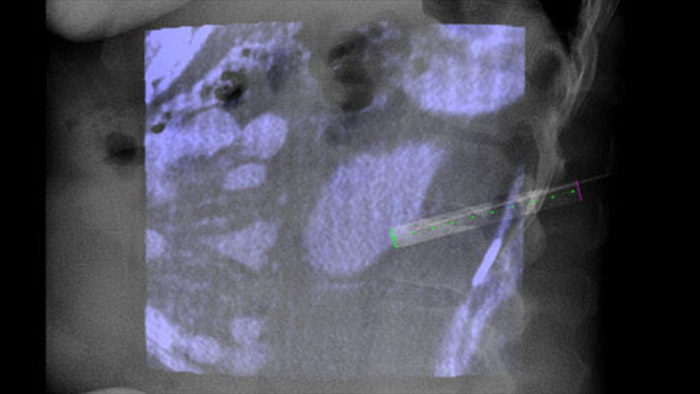

XperGuide fournit un guidage par imagerie en temps réel très précis de chaque aiguille vers une position cible en superposant les trajectoires préplanifiées avec l’imagerie fluoroscopique.3

Grâce à CBCT, faites l’acquisition d’une image CBCT après ablation pour démontrer l’étendue de la couverture tumorale et confirmer l’exhaustivité du traitement.

L’ablation percutanée (radiofréquence, micro-ondes et cryoablation) est un traitement peu invasif bien établi des tumeurs des reins, du foie, des poumons et des os. Il est essentiel de définir les limites de la tumeur et de décider d’un nombre optimal d’aiguilles et de la trajectoire d’aiguille correspondante afin de pouvoir effectuer un traitement complet de la tumeur sans endommager les tissus environnants.